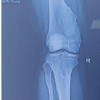

Immediate Post-op X-ray of right knee was done which showed stable fixation and satisfactory alignment. ( Fig. 8)

Figure 8: Immediate post-operative X-ray of right knee.